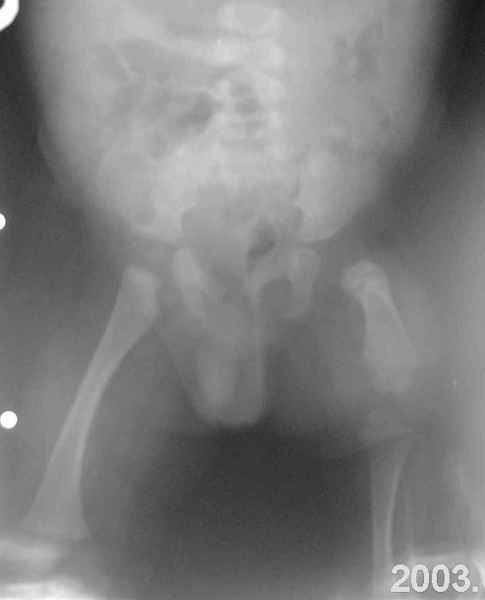

Извините за задержку(по техническим обстоятельствам) еще просим извинения за ошибки (трудный перевод). Больной с врожденной гипоплазией проксимальной части бедра, с ацетабулярной дисплазией. В 6 лет первая операция по стабилизации тазобедренного сустава прилагаю Рг. К нам обратился в следующей ситуацией:укорочение на 26см нижней конечности, соха flecta - 45 °.подвижной до 100°, genu flexum 25-30° мобильный до 90°. Активность мышц бедра- очень слабое, мышцы голени и сама голень отстающей в развитии. В настоящее время пациент ходит самостоятельно с протезом. Спасибо всем еще раз за присланные варианты лечения.Rx при рождении:ниже